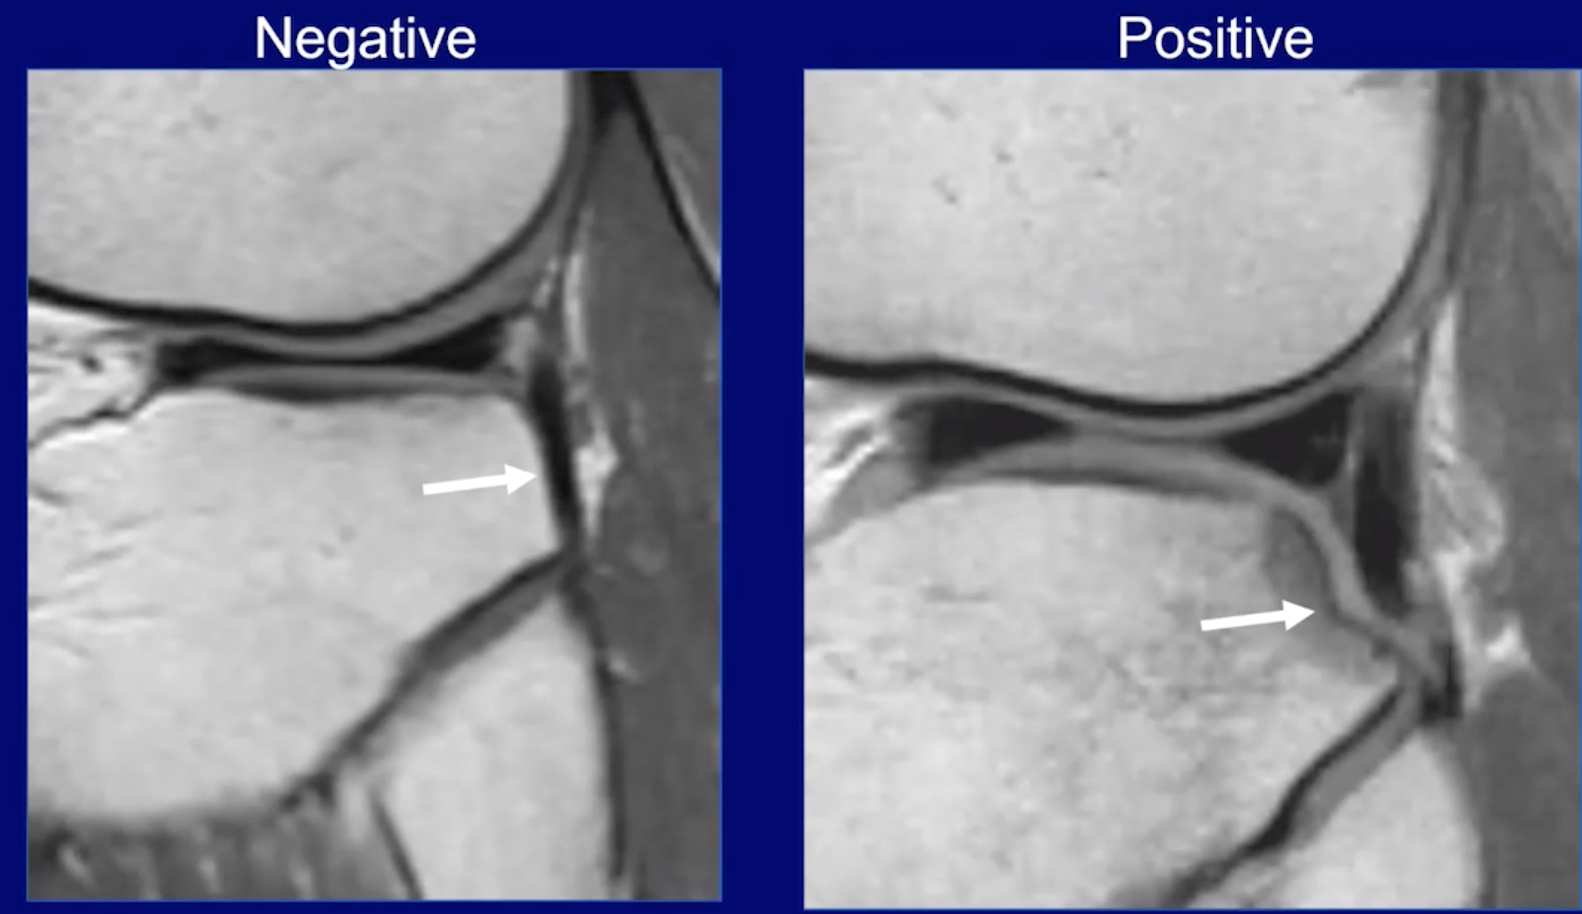

• Abnormal PCL sign

• ACL tear causes PCL to become lax and lose normal configuration and now does not have the normal slope it should have which is a sign of ACL injury

• Anterior tibia translation

• Look for uncovering of lateral meniscus

• Ligamentum mucosa injury (red circle)